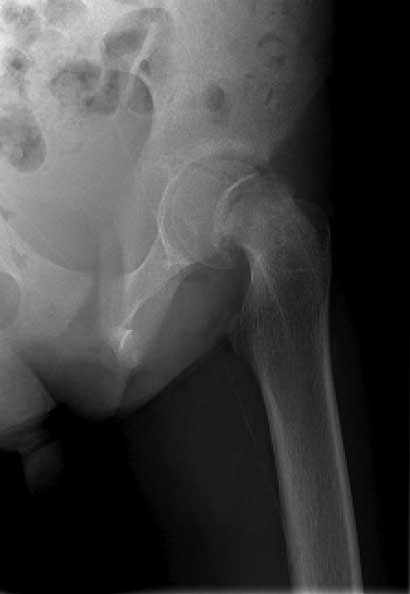

Severe slip treated with arthroscopic Dunn type of femoral neck osteotomy

Severe slip treated with arthroscopic Dunn type of femoral neck osteotomy, reduction and fixation.